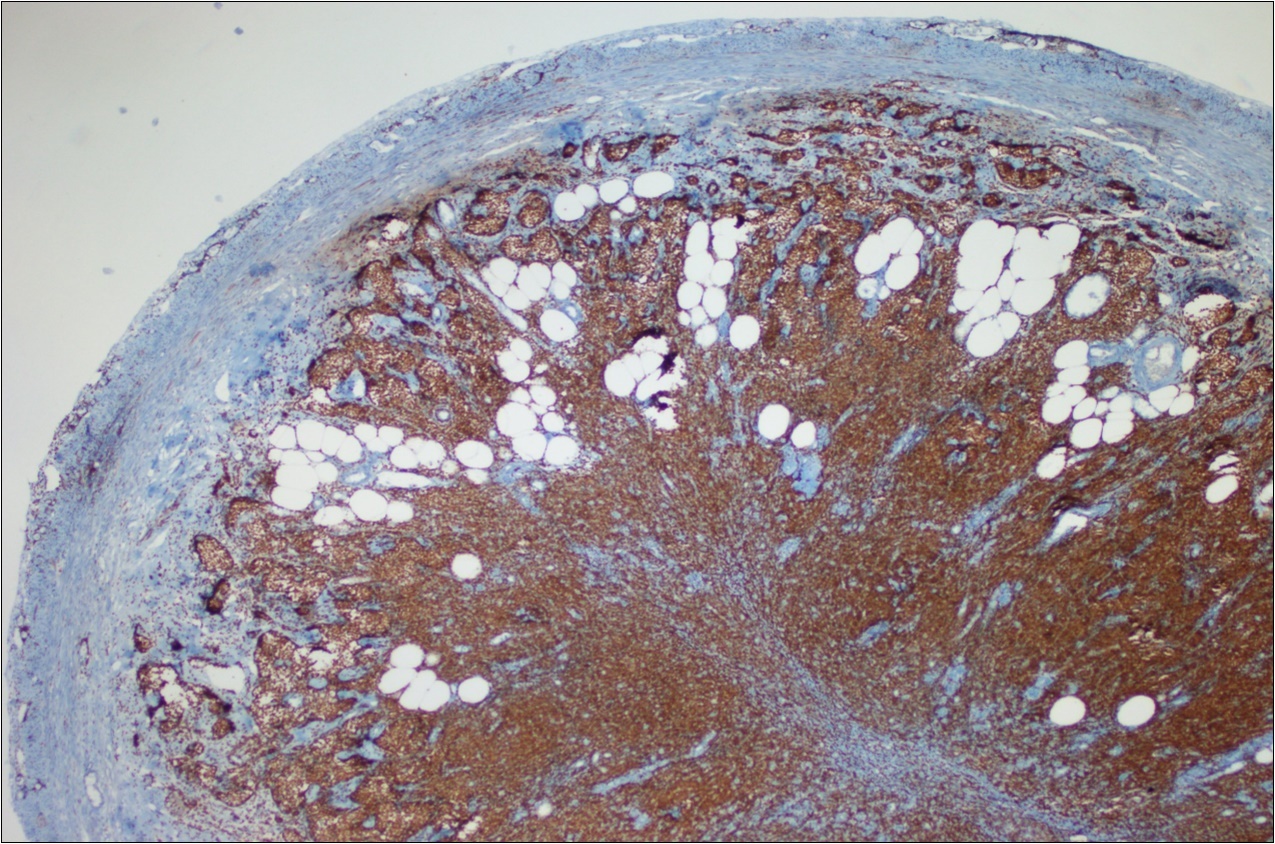

A 63-year-old woman presented to the Department of General Surgery as an outpatient with abdominal pain. Physical examination showed the signs of acute appendicitis and appendectomy was performed. During microscopic examination, a small focus of atypical monotonous lymphoid cell population was seen and the material was sampled totally. The pathological examination revealed MALT lymphoma (Figure 1), with diffuse positivity of cluster of differentiation (CD) 20 (Figure 2), CD 79a and B-cell lymphoma (Bcl- 2) (Figure 3) with just a few CD3 positive lymphoid cells. However, no evidence of adenocarcinoma was found in the appendectomy specimen. After the diagnosis of lymphoma, a complete colonoscopy was planned and this revealed a solid tumoral mass in the caecum measuring 5x4x4 cm. Computed tomography of the abdomen and pelvis revealed mesenteric lymphadenopathy associated with a mass in the caecum with multiple nodules in liver consistent with metastasis (Figure 4). Frozen sections were not obtained since the treatment method would not be affected. The patient underwent anterior resection with regional lymphadenectomy, with the pathological assessment of the resected specimen revealing a collision tumor consisting of a poorly differentiated adenocarcinoma extending through the muscularis propria with MALT lymphoma (Figure 5). Microscopic evaluation of the 11 regional lymph nodes in the mesentery of the resected colon and liver biopsy showed diffuse infiltration of MALT lymphoma with metastasis of adenocarcinoma (Figure 6). According to immunohistochemistry, atypical lymphocytes were positive for CD 20, Bcl-2, and negative for CD3, CD5, CD10, CD23, Bcl-6, terminal deoxynucleotidyl transferase, and cyclin D1. The proliferation fraction (MIB-1 immunostaining) was approximately 20%. The morphological and immunohistochemical findings were used to confirm the diagnosis of synchronous presentation of MALT lymphoma and colon adenocarcinoma within the caecum, mesenteric lymph nodes and liver metastases.

Figure 2.CD 20 positivity of lymphoid cells (CD20, x200)